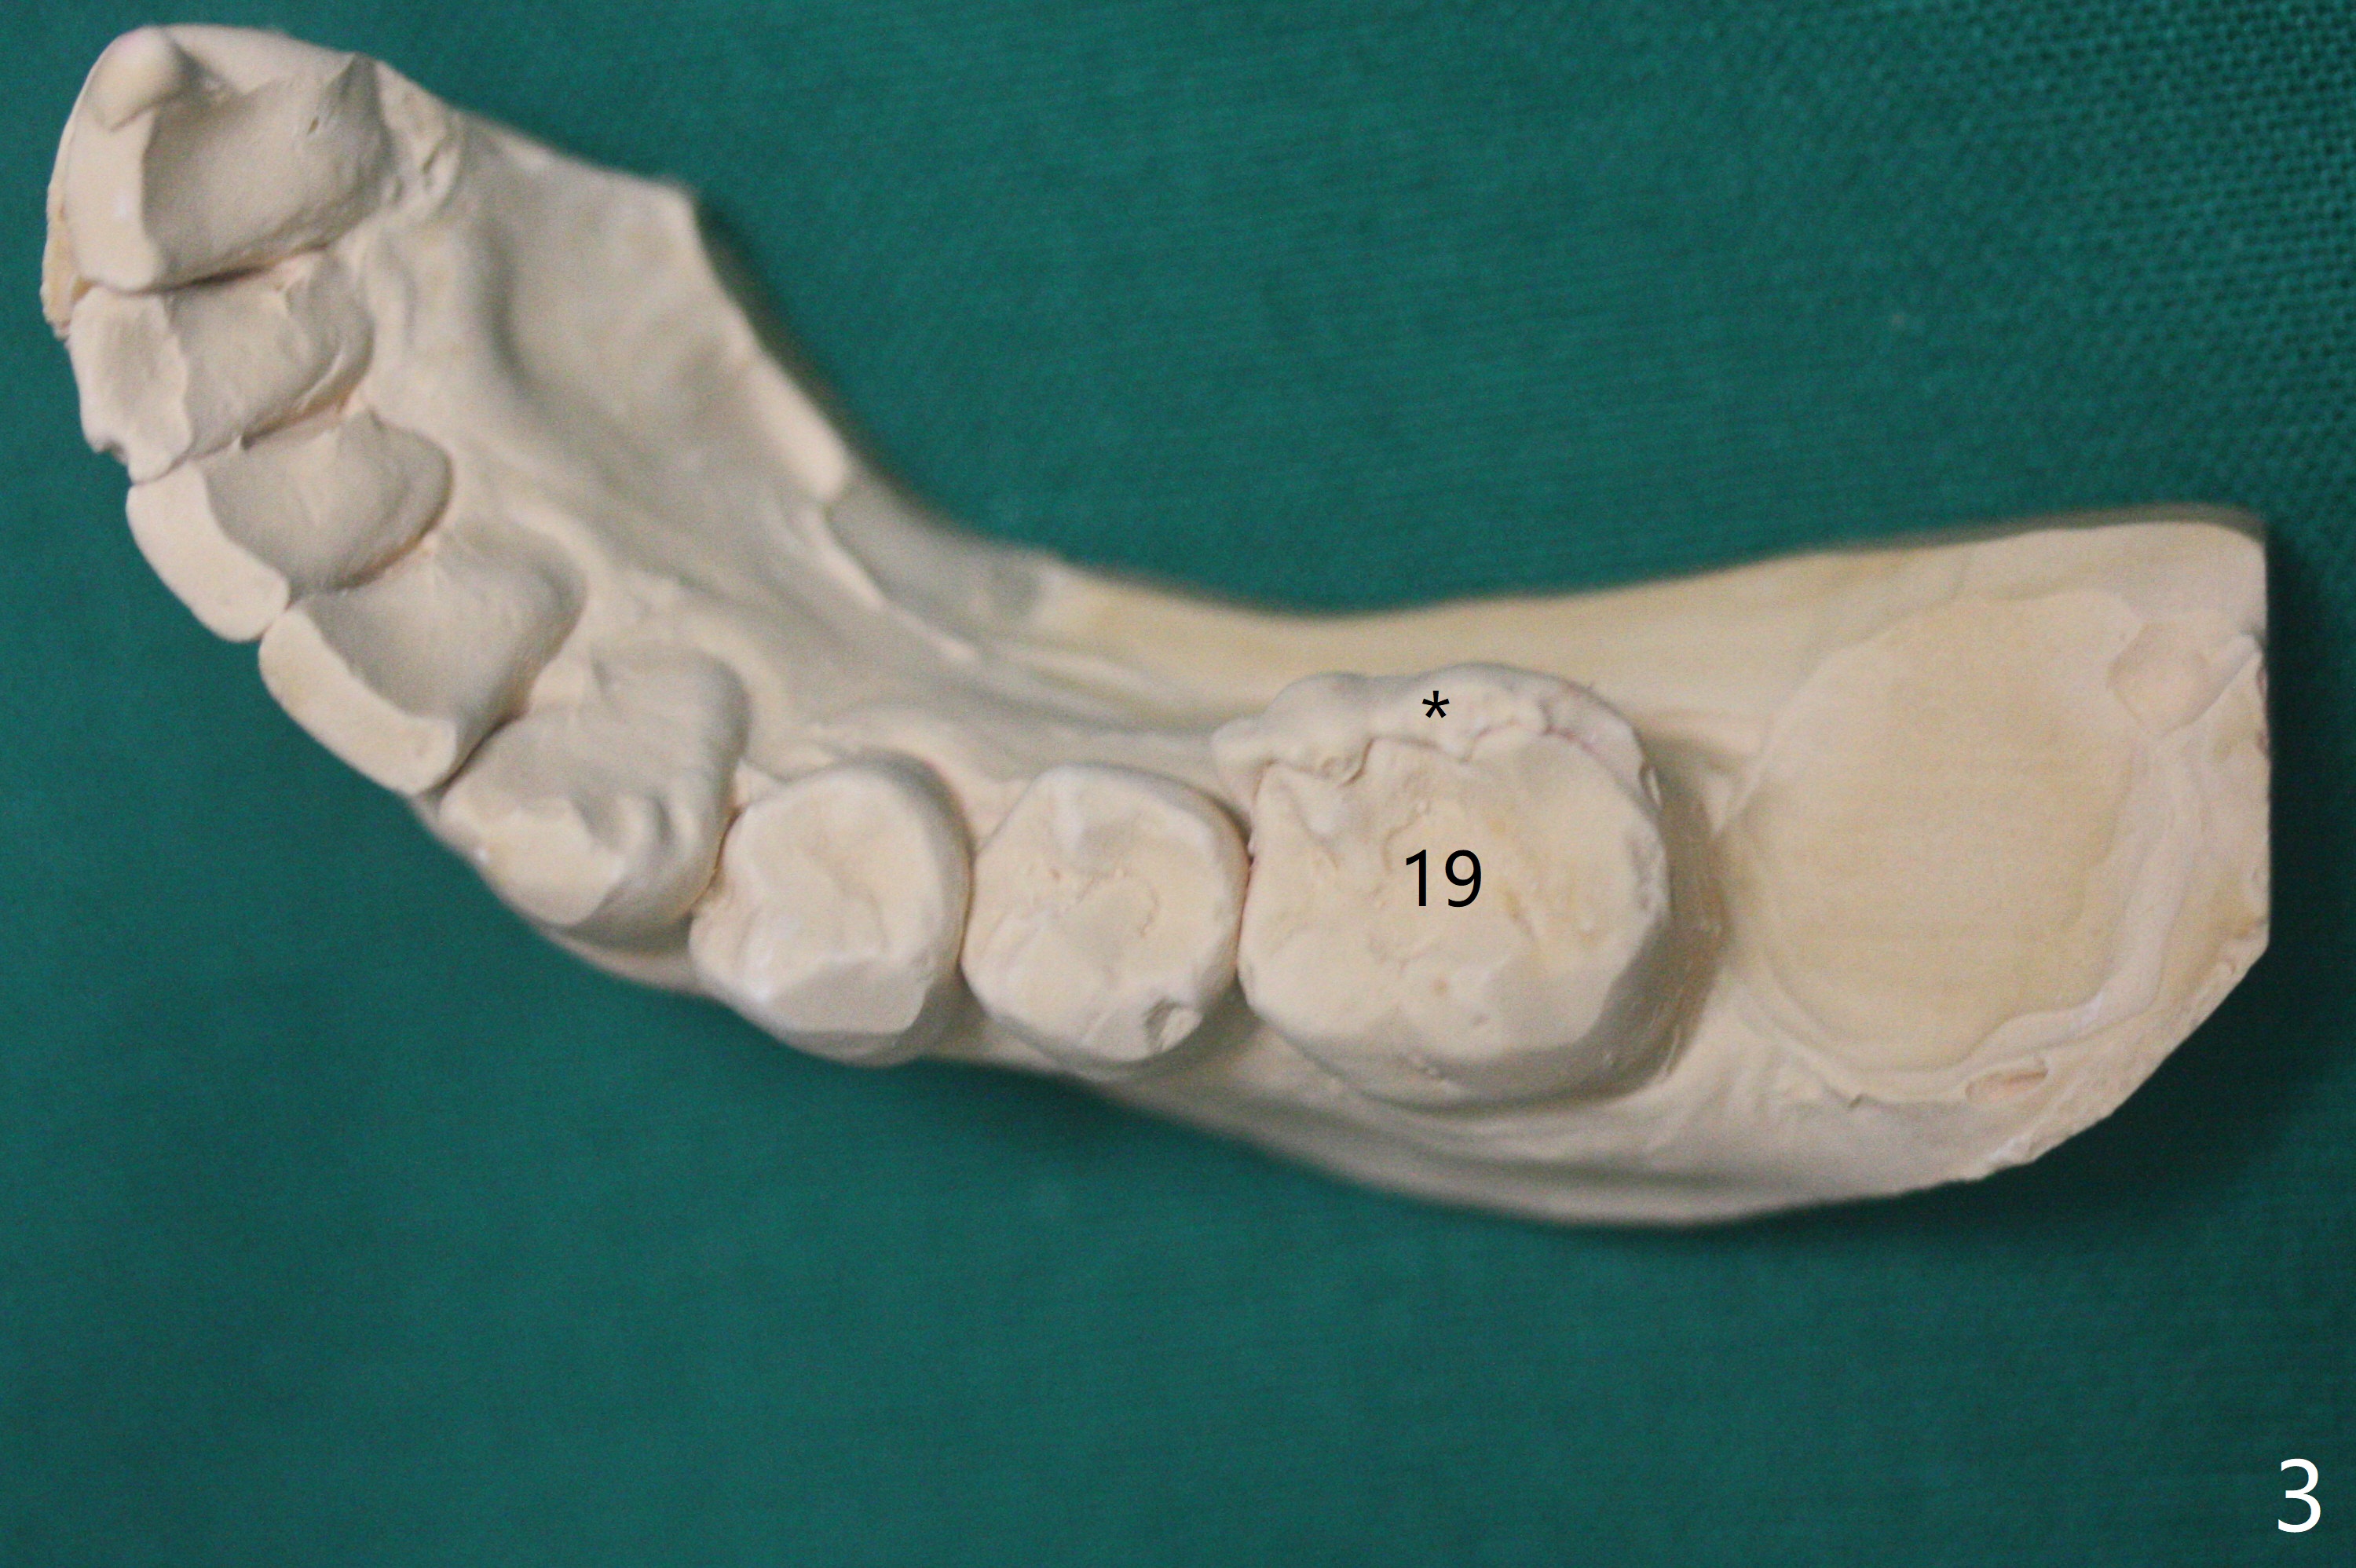

病人舌头大,取模时19号牙舌侧不全(图三),导板制作就没有覆盖舌侧(图四),导板向舌侧倾斜,不准确,植牙就太偏颊侧(图一)。取出植体还必须做近中颊侧切口,放置粘性骨粉和PRF膜(图二:*),PGA缝合,牙周胶水。